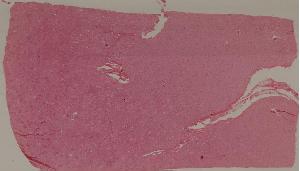

74. Crescentic glomerulonephritis